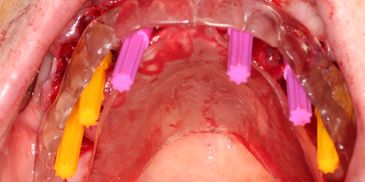

The prosthodontic phase involves the fabrication of the teeth (prosthesis) that attach to the implants. This happens in two stages: the Temporaryand the Final.

Stage A: Immediate Loading (The Temporary Prosthesis)

Digital surgical guides for dental implant surgery bring a new level of precision and predictability to the procedure. These guides are custom-made based on 3D imaging and advanced planning software, ensuring implants are placed with optimal accuracy, minimizing risks, and enhancing patient safety. With digital guides, the placement process is faster, less invasive, and requires smaller incisions, leading to reduced discomfort and quicker healing times. Additionally, digital planning allows for better visualization of complex anatomy, enabling personalized treatment plans tailored to each patient’s unique needs. This technology elevates the quality and outcomes of dental implant procedures, making it an ideal choice for patients seeking the best in dental care.

Dental implant surgery with digital surgical guides begins with a detailed 3D scan of the patient’s mouth, allowing for precise visualization of the jawbone, nerves, and other critical structures. Using specialized software, the ideal implant placement is planned digitally, considering the patient’s specific anatomy and prosthetic requirements. Once the plan is finalized, a custom guide is 3D-printed, designed to fit securely in the patient’s mouth. During surgery, this guide directs the placement of the implant to match the exact planned position, angle, and depth. This approach enhances accuracy, reduces the need for large incisions, and streamlines the procedure, promoting faster recovery and more predictable outcomes.

Digital surgical guides are particularly indicated for complex implant cases, where precise positioning is critical, such as in patients with limited bone structure, proximity to nerves, or aesthetic demands in the front teeth. They are also ideal for full-arch reconstructions and cases with multiple implants, ensuring accuracy and minimizing complications. As technology advances, the future of these guides looks promising. Enhanced AI-driven planning, improved materials, and seamless integration with digital workflows will make surgical guides even more adaptable, efficient, and accessible. With ongoing innovation, digital guides are set to become a standard in implant dentistry, ensuring high precision and superior patient outcomes.